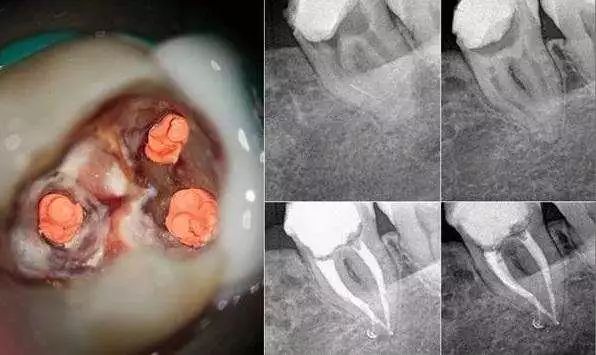

通过一组病例来了解下:

- 术前X光片:红圈处清晰显示牙体龋坏,已影响牙髓,需做根管治疗

- 术后X光片:显微镜下热牙胶根管治疗后,可见充填严密到位

1.测量根管长度。通过X光、根管长度测量仪等工具确定根管的准确长度,以保证清洁时可以触及牙根内全部区域,达到最佳的清洁效果。

通过X光确认根管长度

3.使用根充材料将根管密封填充。当用根管锉将根管内部清洁干净后,牙医会用不可吸收、并且在X光上会显影的材料将根管填满封死。

根管填充